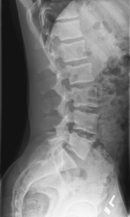

• Recumbent in true lateral position, flex hips and knees, align and center midaxillary plane to centerline

• Place support under waist as needed to place entire spine parallel to tabletop (see Note). Provide support between knees.